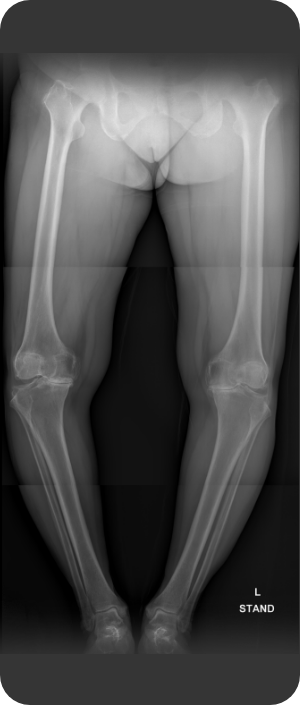

무릎인공관절 전치환술 사례1

• ▲ 수술 전

• ▲ 수술 후

무릎인공관절 전치환술 사례2